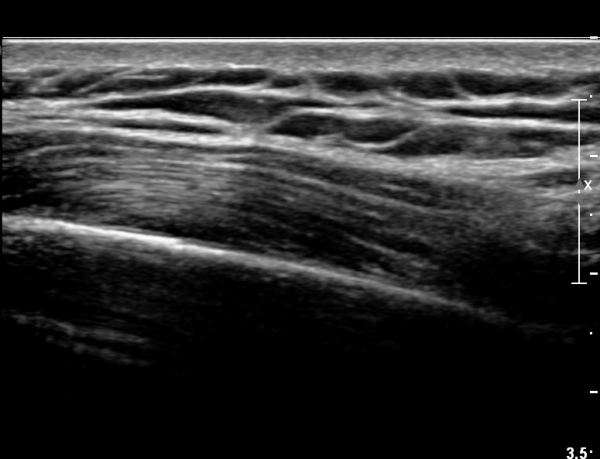

8¹øÂ° °¥ºñ»À ¾ÕÂÊ Á¾´Ü¸é°Ë»ç»ó ƯÀÌ ¼Ò°ßÀ» º¸ÀÌÁö ¾ÊÀ¸¸¶(»çÁø 4)

ŽÃËÀÚ¸¦ µÚÂÊÀ¸·Î À̵¿ ÇÏ´Ï °¥ºñ»À Ç¥ÃþÀ¸·Î Àú¿¡ÄÚ ºÎÁ¾ÀÌ °üÂûµÈ´Ù(»çÁø 3).